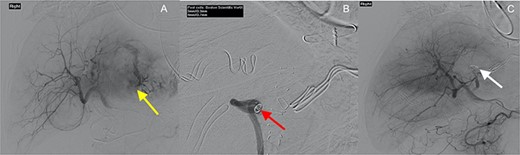

Interventional angiography of the liver (yellow arrow—extravasation of contrast, red arrow—coils placed in segment II/III artery and white arrow—coil in segment II/III artery with no evidence of contrast extravasation).

On arrival to the tertiary centre, the patient was admitted to an intensive care unit for ongoing resuscitation. The patient subsequently underwent selective angioembolization of a segment II/III artery using polyvinyl alcohol (PVA) particles (250–350 μm) and four micro-coils (Fig. 2). Seventy-two hours after presentation, the patient underwent a re-look laparotomy with a left lateral sectionectomy of the liver to resect the identified lesion.